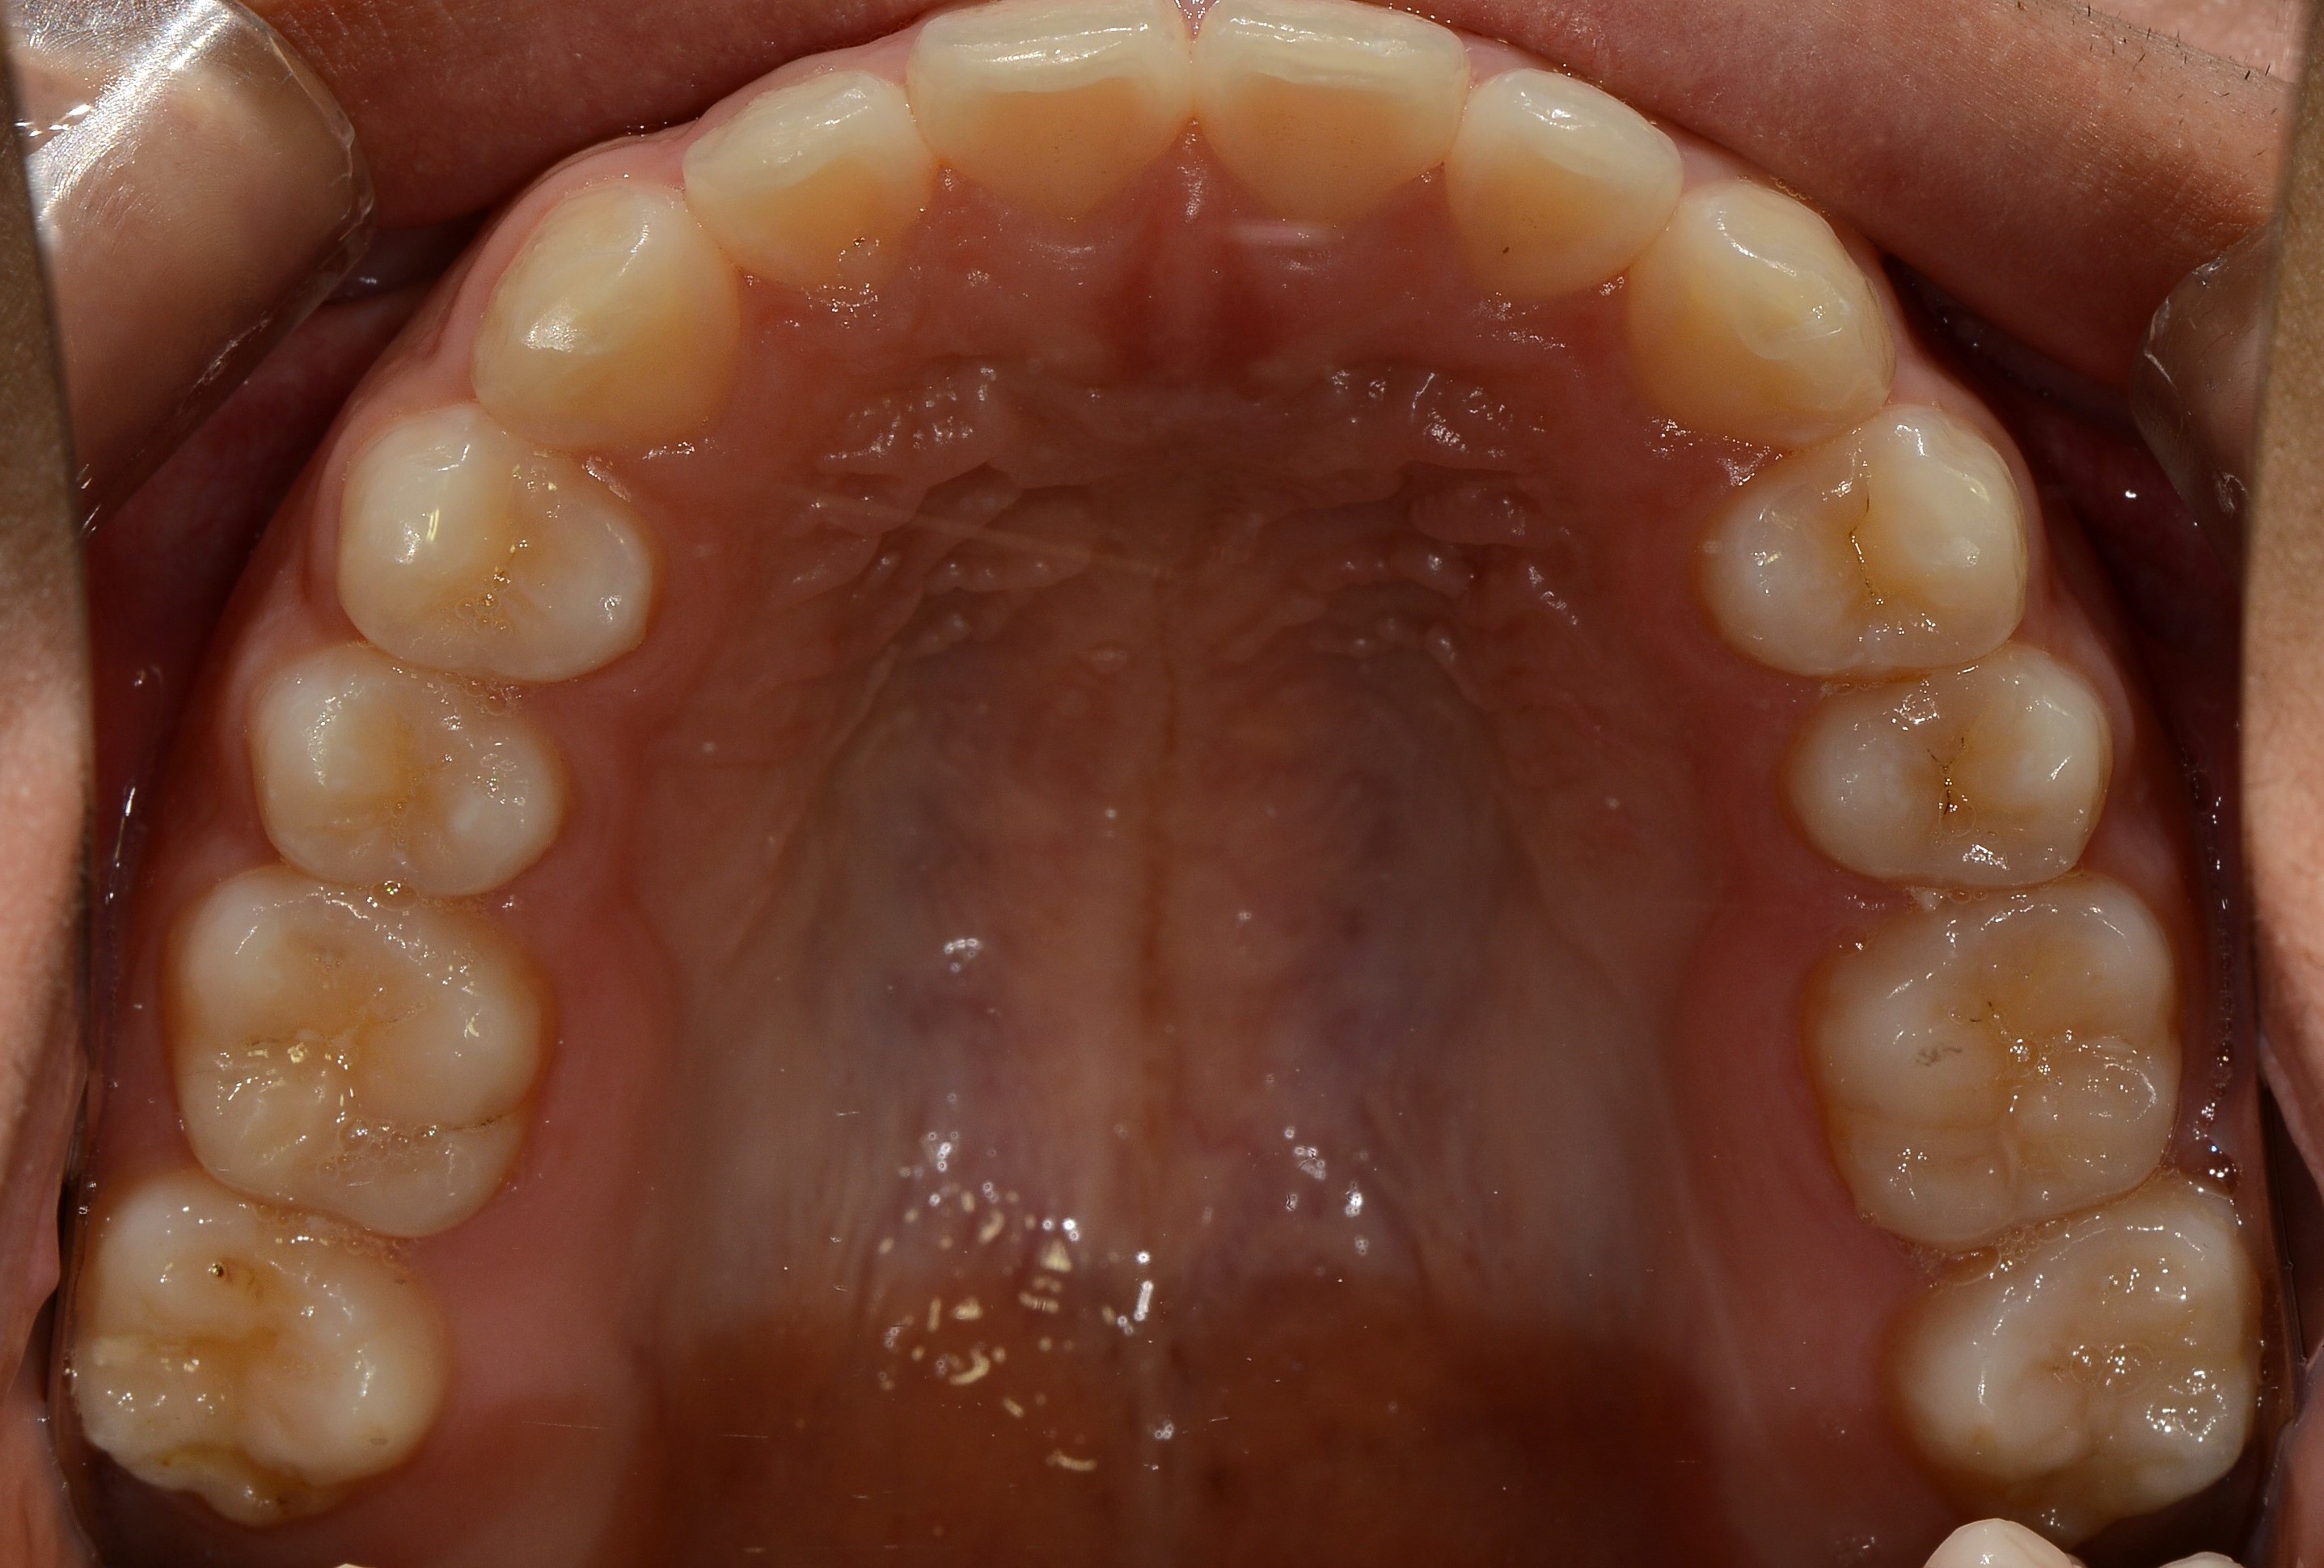

치료 전 사진입니다.